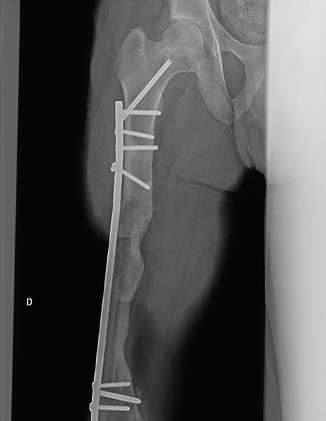

Neste estudo, os pacientes sofreram traumas graves, com perdas ósseas e de partes moles, realizaram múltiplas cirurgias e tiveram longos períodos de reabilitação, e apesar de tudo isso alcançaram bons resultados. Acredita-se que este resultado também esteja relacionado com o início precoce do programa de reabilitação. No paciente que apresentou melhor resultado (Figura 1), observou-se consolidação óssea, com hipertrofia significativa da fíbula, amplitude de movimento da articulação do joelho em 110° e marcha com uso de bengala para meio externo, devido a sua insuficiência do mecanismo extensor do joelho. Portanto, atingiu uma recuperação funcional adequada, onde consegue realizar atividades como subir e descer escadas sem dificuldades e conseguiu retornar ao mercado de trabalho.

Figura 1 - Radiografia de um dos pacientes do estudo. a: raio-x inicial com fratura de fêmur. b: fíbula vascularizada implantada 1 ano após o trauma. c: 6 anos após a fíbula vascularizada com consolidação óssea evidente